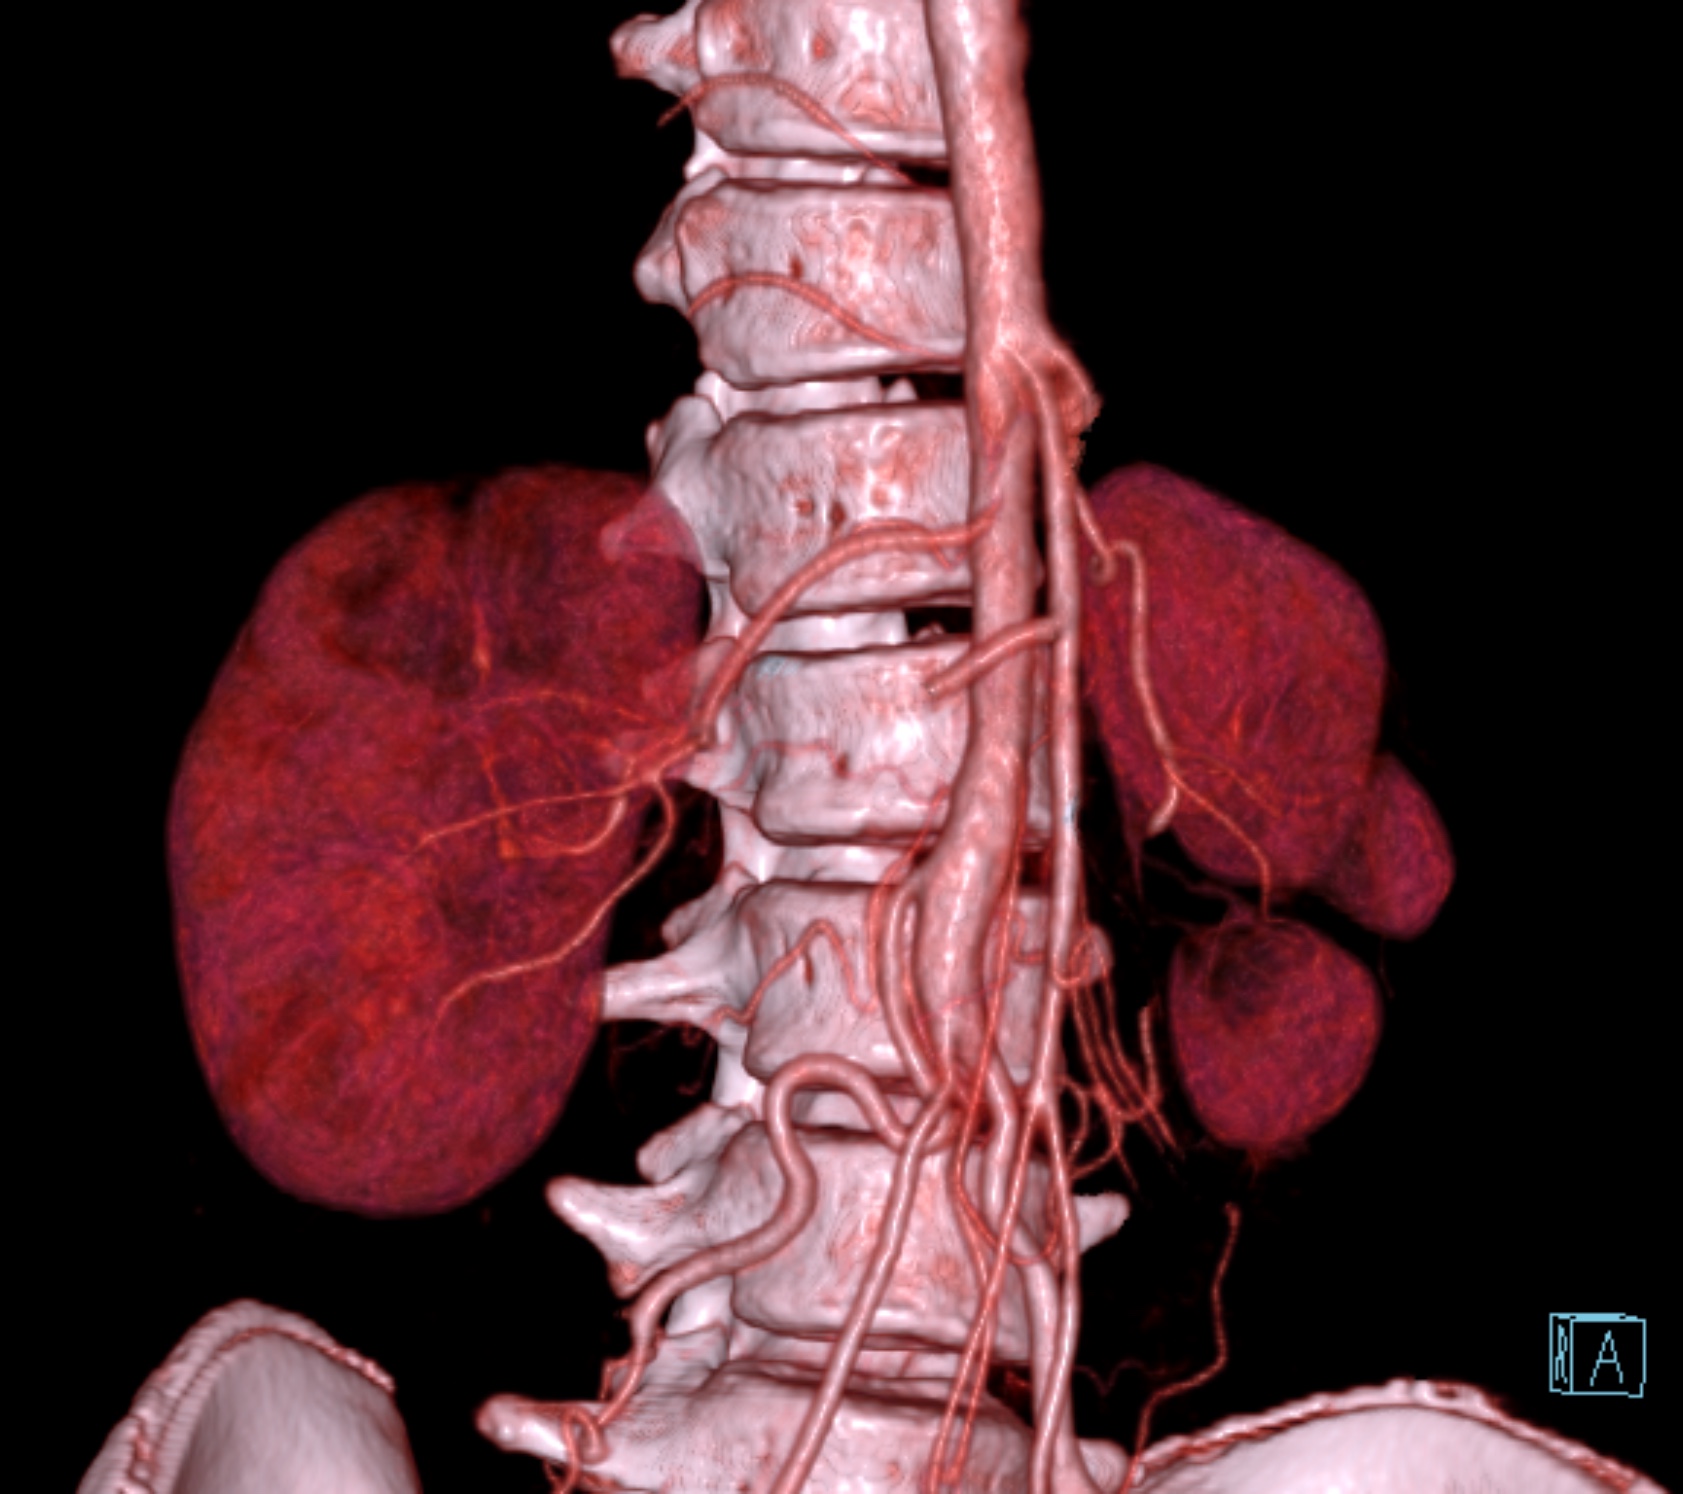

Echocardiogram showed preserved left ventricular ejection fraction with mild aortic regurgitation without residual VSD. Laboratory results showed normal renal function with estimated glomerular filtration rate of more than 75. Computed tomography angiography showed significant stenosis at the ostium of right renal artery.

Six french femoral arterial sheath was placed under ultrasound guided. Renal angiogram using 6 Fr Renal Double Curve catheter showed normal left renal artery and subtotal occlusion near at the ostium of right renal artery.